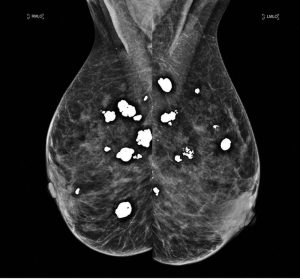

چھاتی کے ٹشوز میں بعض اوقات کیلشیم جمع ہو جاتا ہے۔ میمو گرام میں یہ عام طور پر سفید دھبوں یا چھوٹے ذرات کی شکل میں نظر آتا ہے۔ چھاتی میں جمع کیلشیم (Breast calcifications) بالعموم کینسر نہیں ہوتا۔ یہ زیادہ تر چھاتی کی غیر خطرناک (benign) تبدیلیوں کی وجہ سے ہوتا ہے، تاہم بعض اوقات کچھ غیر معمولی یا جمع شدہ ذرات بریسٹ کینسر یا اس سے پہلے کی تبدیلیوں کی علامت ہو سکتے ہیں۔

چھاتی میں جمع کیلشیم میموگرام میں میکرو کیلسیفیکیشنز یا مائیکرو کیلسیفیکیشنز کی شکل میں نظر آ سکتا ہے۔

میکرو کیلسیفیکیشنز

یہ بڑے سفید نقطے یا لکیر کی طرح دکھائی دیتے ہیں، اور زیادہ تر کینسر نہیں ہوتے۔ ان کے لیے عام طور پر مزید ٹیسٹ یا فالو اپ کی ضرورت نہیں ہوتی۔

مائیکرو کیلسیفیکیشنز

یہ باریک سفید ذرات نمک کے دانوں کی طرح دکھائی دیتے ہیں۔ بعض پیٹرنز کینسر کی ابتدائی علامت ہو سکتے ہیں۔